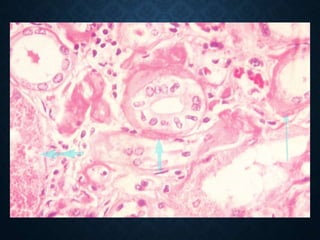

ATHEROSCLEROSIS

• Monocytes adhere to damaged endothelial

cells, pass between them and settle

subendothelially

• Here they turn into macrophages that accept

lipoproteins, mainly low-density lipoproteins

(LDL) and form the so-called foam cells.

Foam cells

Cholesterol crystals